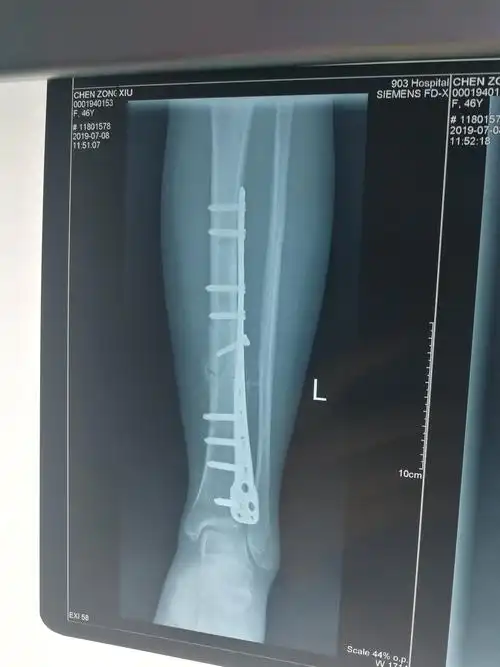

胫腓骨折3个月及取钢板后续

小腿下端胫腓骨骨折75天终于长骨痂了!

术后2月骨痂生长良好